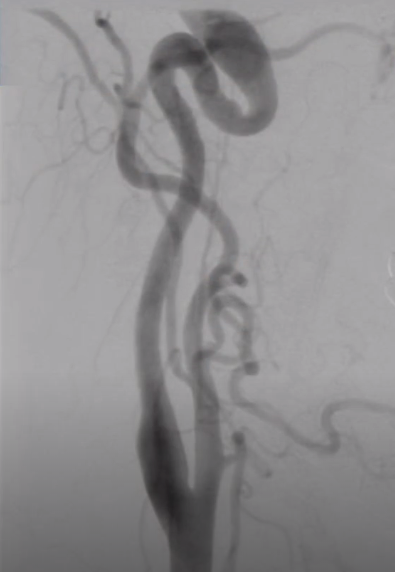

➤ 中膜纤维组织增生的典型表现——串珠样狭窄改变

图7 55岁女性,表现为难以控制的高血压,肾动脉和颈内动脉中-远段呈串珠样狭窄改变,串珠直径大于正常血管腔